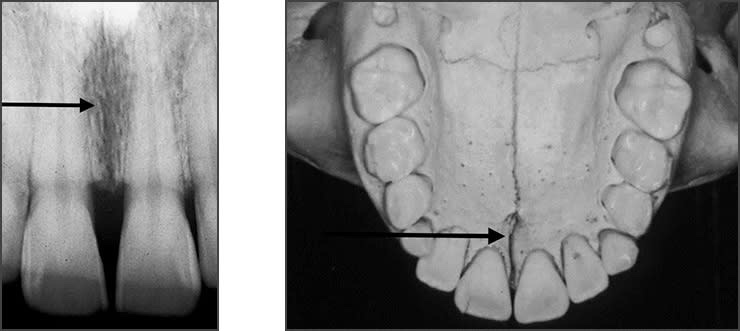

• Intermaxillary suture – Immovable b/w two palatine process of maxilla.

• Incisive foramina – Nasopalatine vessels & nerves lies in midline on lingual aspect of hard palate. Radiographically, it appears between the roots of the central incisor teeth as a round to oval radiolucency less than one centimeter in diameter.

• Y line of Ennis – The inverted Y is a radiographic landmark that depicts where the nasal fossa crosses the maxillary sinus. The boundary between them is shaped like an upside-down letter Y, hence its name.